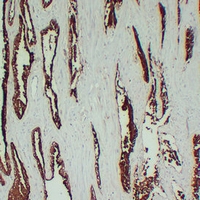

(Immunohistochemical analysis of TMPase staining in human prostatic carcinoma formalin fixed paraffin embedded tissue section. The section was pre-treated using heat mediated antigen retrieval with sodium citrate buffer (pH 6.0). The section was then incubated with the antibody at room temperature and detected using an HRP conjugated compact polymer system. DAB was used as the chromogen. The section was then counterstained with haematoxylin and mounted with DPX.)

(Immunohistochemical analysis of TMPase staining in human prostate formalin fixed paraffin embedded tissue section. The section was pre-treated using heat mediated antigen retrieval with sodium citrate buffer (pH 6.0). The section was then incubated with the antibody at room temperature and detected using an HRP conjugated compact polymer system. DAB was used as the chromogen. The section was then counterstained with haematoxylin and mounted with DPX.)

(Immunohistochemical analysis of TMPase staining in human benign prostatic hyperplasia formalin fixed paraffin embedded tissue section. The section was pre-treated using heat mediated antigen retrieval with sodium citrate buffer (pH 6.0). The section was then incubated with the antibody at room temperature and detected using an HRP conjugated compact polymer system. DAB was used as the chromogen. The section was then counterstained with haematoxylin and mounted with DPX.)